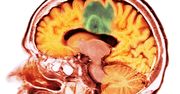

Każdego roku u ponad 2700 osób w Polsce wykrywane są guzy mózgu. Taka diagnoza jest często jak wyrok – według Krajowego Rejestru Nowotworów przeżywa mniej niż połowa pacjentów. Teraz okazuje się, że jest dla nich nadzieja. Naukowcy opracowują szczepionkę, która ma zapobiegać takim schorzeniom.